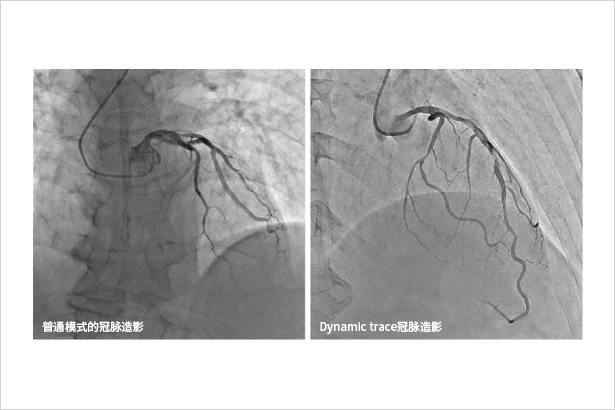

Dynamic trace主要用于下肢造影、心臟介入等影像密度差異較大的介入手術

針對動態透視圖像進行放大成像,比左圖傳統FOV放大不會造成劑量增高